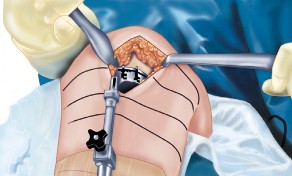

2. الوضع الجراحي والتعرض

- الوضع: يُوضع المريض في وضع الاستلقاء (Supine positioning) مع وضع كيس رمل أسفل الركبة أو حامل للساق يسمح بثني وفرد الركبة. يجب أن يكون الوضع مماثلاً لوضع جراحة TKA، مع استعداد لتحويل الإجراء إلى TKA إذا لزم الأمر.

- العاصبة (Tourniquet): تُستخدم عاصبة وتُوضع في أعلى الفخذ لتقليل النزيف.

-

الشق الجراحي:

يُستخدم شق طولي في الجانب الإنسي (الداخلي) من الركبة. يجب أن يكون الشق كبيرًا بما يكفي لتوفير رؤية جيدة للمفصل الرضفي الفخذي وإمكانية التحويل إلى TKA.

- فتح المفصل (Arthrotomy): يكون الفتح خطيًا وموازياً لألياف الوتر الرضفي، ويمتد إلى عظم الظنبوب وإلى الجزء السفلي من الرضفة.

- تحرير الأنسجة الرخوة: يتم قطع الغضروف الهلالي لتحرير الأنسجة الرخوة من عظم الظنبوب، ويتم تطوير سديلة تحت السمحاق في نمط دائري حول الظنبوب. يُمدد هذا التحرير خلفيًا لضمان توازن الأربطة.

-

تصحيح التشوه:

الهدف هو تحقيق تصحيح طفيف للتشوه، مع وجود رخاوة كاذبة طفيفة عند تطبيق ضغط تفحجي في نهاية الإجراء. يجب تجنب التصحيح المفرط.